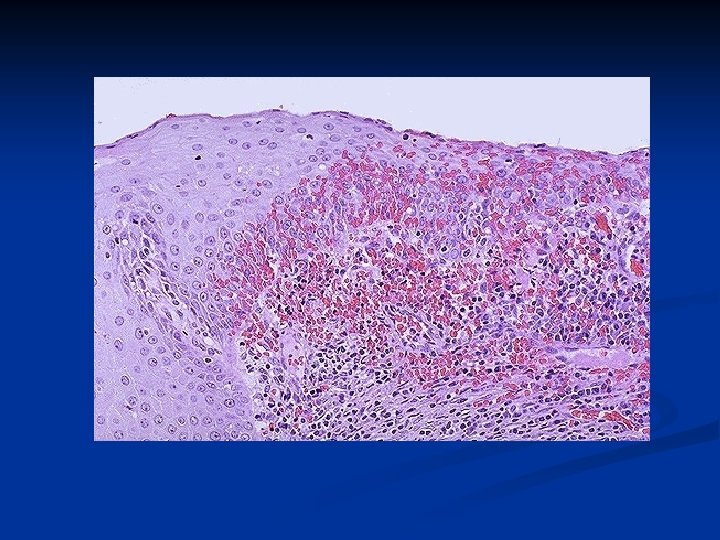

Adenocarcinoma in situ (lower), associated with CIN 3 (upper). Downloaded from: Robbins & Cotran Pathologic Basis of Disease (on 24 February 2006 08: 56 AM) © 2005 Elsevier